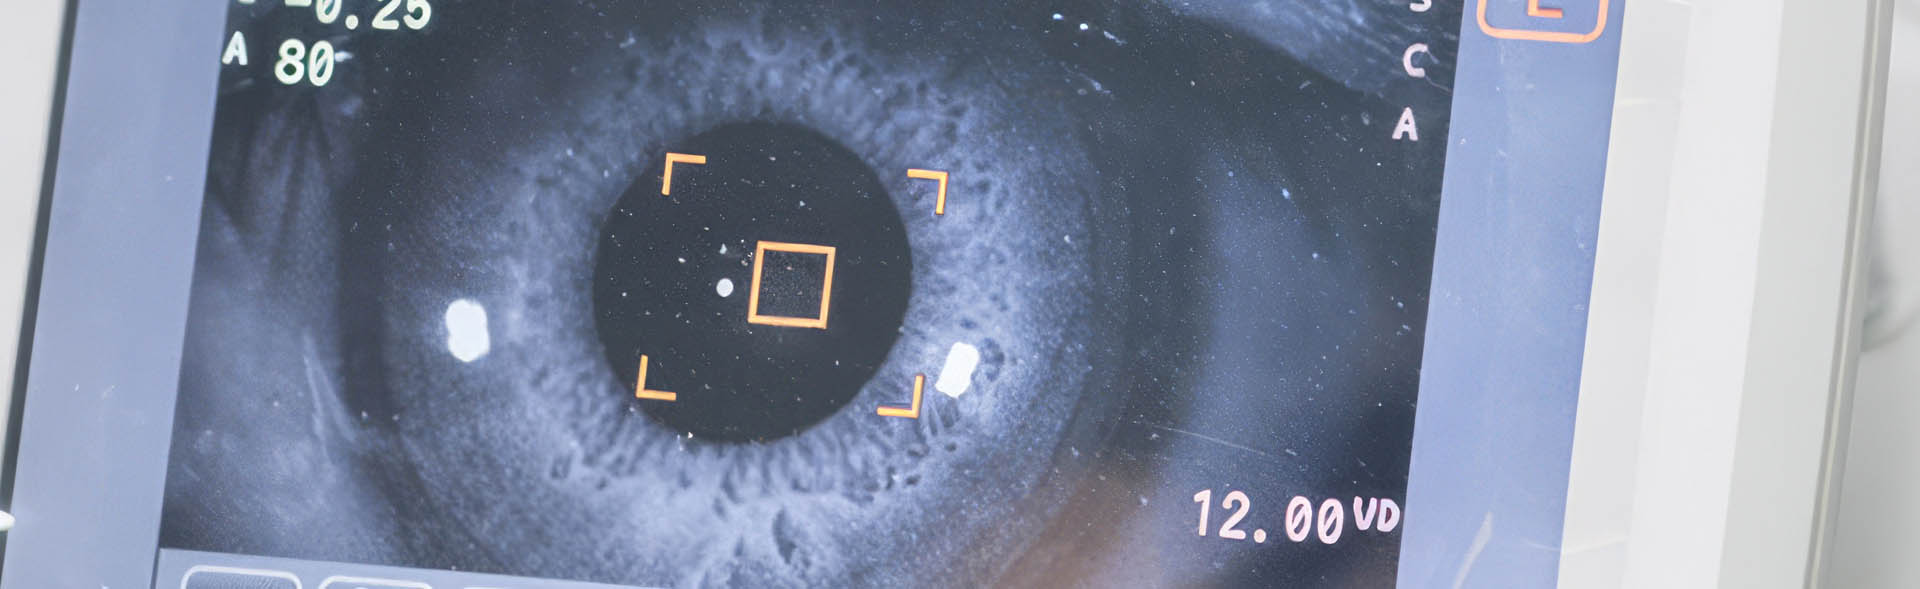

Pregled, dijagnoza i lečenje bolesti žute mrlje (makule) odnose se na savremene oftalmološke procedure koje omogućavaju rano otkrivanje i terapiju promena u centralnom delu mrežnjače. Ove metode se koriste kod oboljenja kao što su makularna degeneracija, kao i kod drugih degenerativnih i vaskularnih poremećaja koji utiču na centralni vid. Dijagnostika uključuje detaljne preglede poput OCT i drugih naprednih snimanja, dok lečenje može obuhvatati intravitrealne injekcije, laser ili hirurške procedure, u zavisnosti od stadijuma bolesti. Cilj je očuvanje i poboljšanje centralnog vida uz individualno prilagođen terapijski pristup.